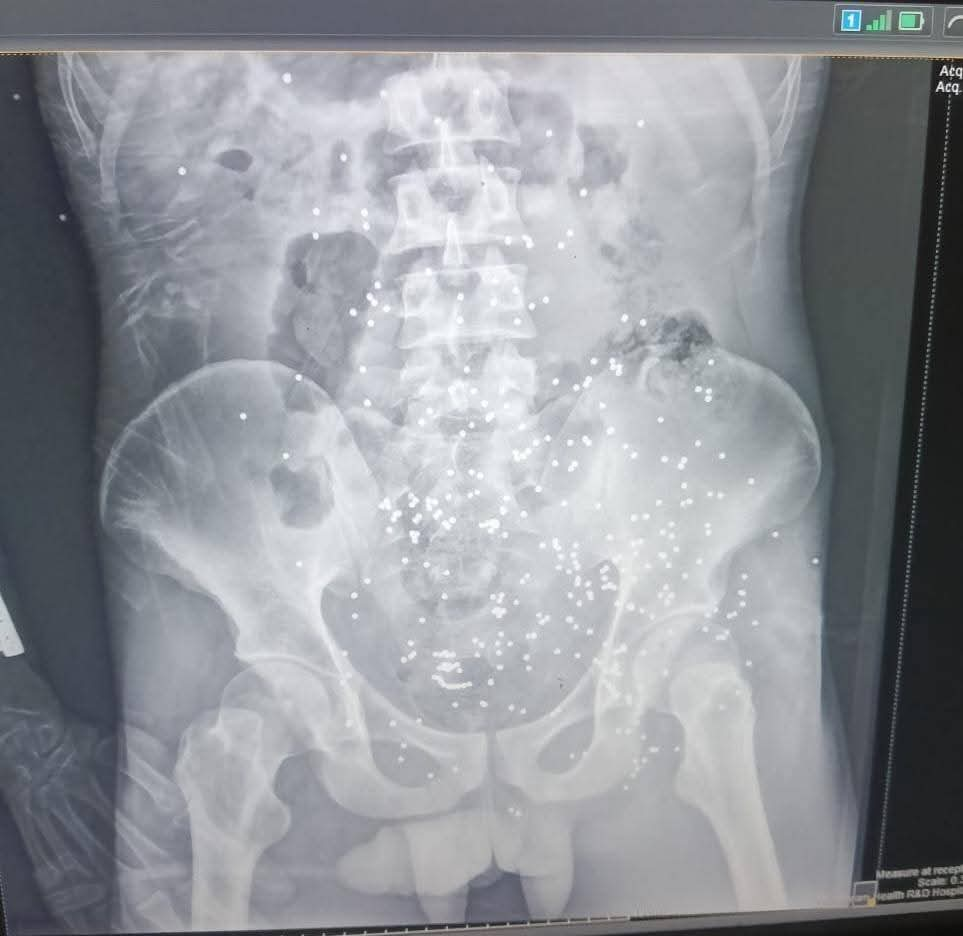

استقبلت طوارئ مستشفى ملوي التخصصي، جنوب محافظة المنيا شابًا في العقد الثالث من عمره، كان يعاني من حالة حرجة نتيجة تعرضه لحادث طلق ناري خرطوش بالبطن.

وأدى هذا الحادث إلى إصابات متعددة في منطقة البطن، مع اشتباه في إصابة الوريد المغذي للطرف السفلي، وكذلك اشتباه في إصابة المثانة ونزيف شديد من أماكن دخول الخرطوش.

وتم إدخال المريض إلى غرفة العمليات مباشرة، حيث قام الفريق الطبي بإجراء استكشاف للبطن، وتبين وجود نزيف داخلي وإصابات في الأمعاء ومساريقا البطن.. استمر العمل الجراحي لمدة خمس ساعات، حيث بذل أطباء الجراحة والتخدير جهودًا كبيرة للحفاظ على حياته.